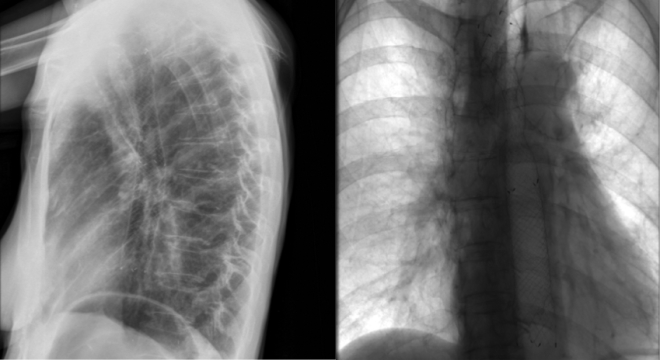

El proceso se realiza bajo control endoscópico y radiológico y con el paciente bajo sedación profunda.